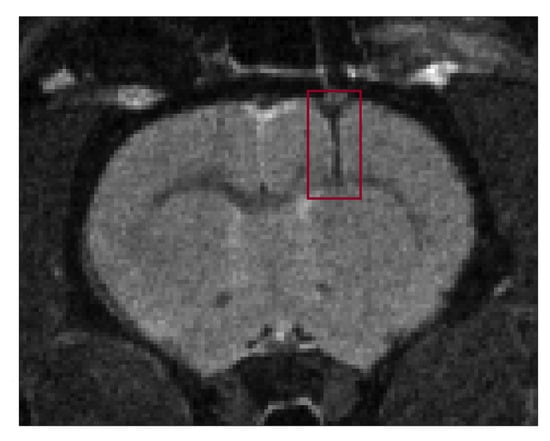

An anatomical MR T 2 -weighted image of the healthy rat brain shows the positioning of the implantable microcoil and the acquisition voxel (Figure 2).

Figure 2. Visualization of the implantable microcoil and the PRESS voxel in anatomical T 2 -weighted MR image of the healthy rat brain.